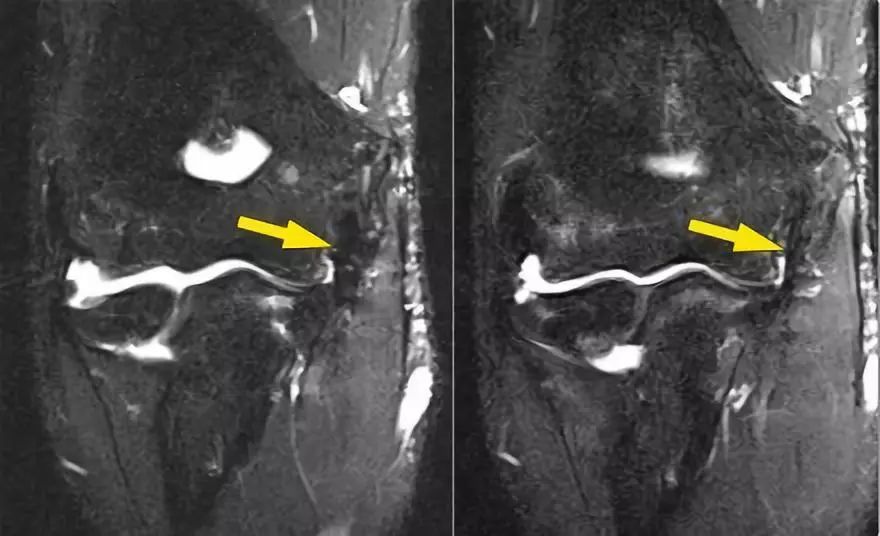

下面的图我们看到UCL的两个连续冠状图像。在近端部分(箭头)看到一些高信号是正常的。注意它是如何牢固地附着在崇高的结节上并将其与下一个图像进行比较。

请记住,UCL应该非常紧密地附着在崇高的结节上。在下面这种情况下它没有,所以即使在这两个图像上你也可以看出它有完全的撕裂。请注意,崇高结节中存在一些骨髓水肿。